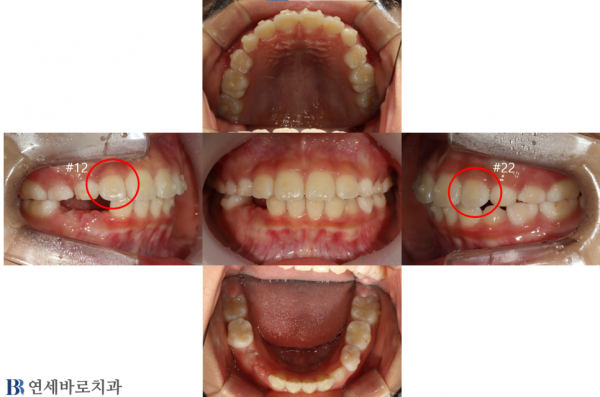

인비절라인을 이용한 소아 교정 사례입니다.

인비절라인의 경우 투명교정장치를 사용하여 기존 교정장치의 불편감과 눈에 보이지않아

심미적으로도 좋은 교정 치료 방식입니다.

After의 아랫니는 유치가 발치된 상태로 영구치가 자라날수 있는 공간도 확보 후 치료를 마무리 하였습니다.

촬영시기: 22.08.08(전) 23.11.04(후)